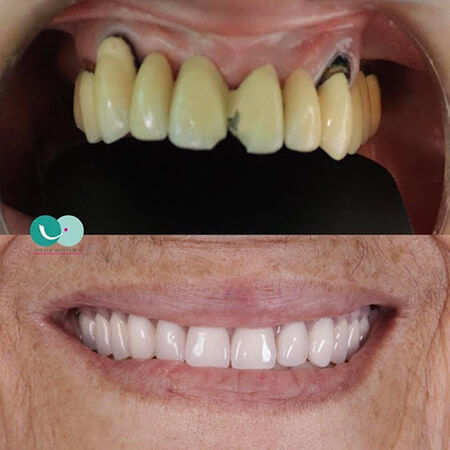

Before and After Gallery

Estoy completamente felizzzz , me realizaron implantes con coronas de Zirconio y láminas en cerámica en los dientes de adelante superiores y tuvo el mejor cuidado para complementar el color de mi dentadura de manera muy perfecta , la felicidad es toda , demasiado profesional y ética , estoy completamente feliz , Me hizo otros tratamientos donde implicaba mucho tiempo y la constancia y dedicación me sorprendió y lo logró en el menor tiempo posible , es sorprendente su empatía con el paciente, muchas gracias Doctora Eva